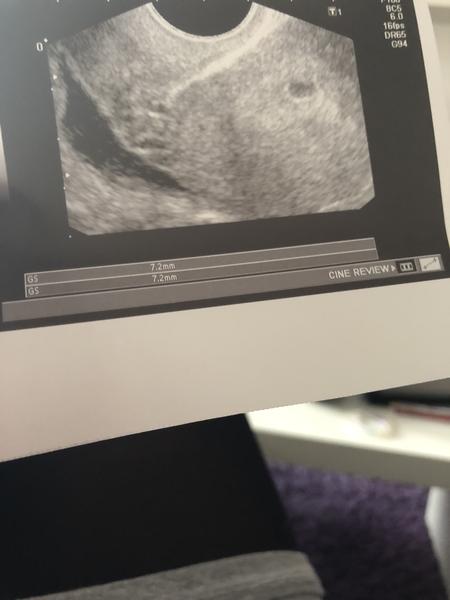

Ahoj holky, mohla bych vas poprosit o radu? Byla jsem dnes u doktora, protoze se mi opozdila menstruace, kterou jsem mela dostat uz 12.1. Delala jsem si minuly tyden 2 testy a byly na nich dve carky i kdyz slabounke. Predtim 4 testy a na nich nic.Mela jsem uz takovou radost, ale doktor mi rekl, ze je jeste moc brzy a objednal me na 20.2. To uz pry budeme vedet, jestli je tam srdecni cinnost. Dal mi i fotku z ultrazvuku, ale je na ni jen GS 7,2 mm. Upne nevim, co to znamena. Jestli je uz ted neco spatne nebo neni? Asi me nechtel strasit, ale pak zminil taky neco o nemocnici, ale ze to je jeste moc brzy a musime pockat, ze me nechce strasit.Fotku posilam taky.